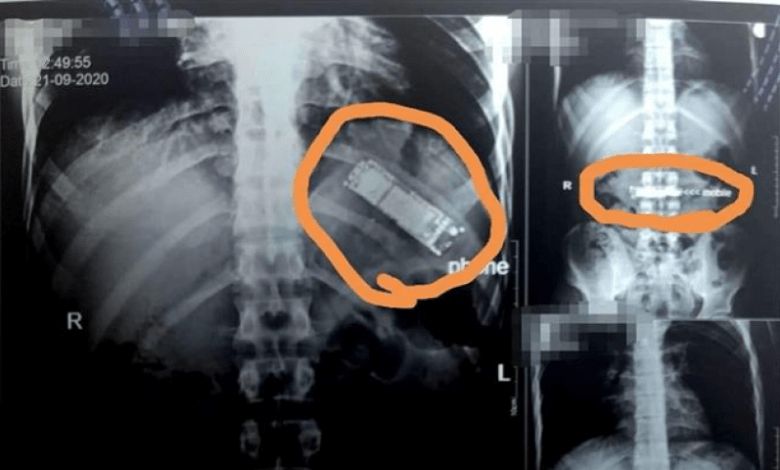

واستقبل المستشفى مريضا يعاني من ألم شديد في البطن فأجريت له أشعة وفحوصات طبية كشفت عن وجود التهابات شديدة في البطن والأمعاء، فقرر الأطباء فتح غرفة العمليات فورا لإنقاذ حياة المريض.

وعلى الفور، قام طاقم الجراحة بمستشفى أسوان الجامعي بإجراء عملية، وقاموا باستخراج جسم غريب من معدته، تبين أنه هاتف جوال صغير حيث قام الفريق الطبي باستخراج الهاتف من معدة المريض، وهذه تعد الواقعة الأولى من نوعها.